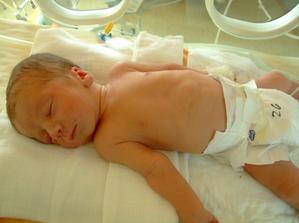

Nová naděje. Bohužel to bylo opět stejné, jako již dvakrát předtím. Třetí revize, třetí ztráta naděje. Jsem po laparoskopii a hysteroskopii a čekáme na výsledky imunologie v Plzni. Pak se uvidí co dál. V únoru 2009 nám v Sanusu doporučili ještě dva měsíce domácího snažení. Tak jsme se snažili a nyní napjatě sledujeme čárku. HCG nám krásně stoupá, 20. den po ovulaci je 2066. Máme 1. fotku dutinky. Přes nejrůznější potíže a patnáctidenní hospitalizaci nám miminko krásně roste. 22. dubna konečně po čtrnácti dnech ukázalo nosánek, máme nosní kůstku, NT je 2,0. Máme vše, co máme mít a rodiče se dnes poprvé společně dívali na ultrazvuk. Viděli mě i 4D, to koukali. Odnesli si video a teď na něj pořád koukají. Další kontrola náš čeká 5. května, opět ultrazvuk, triple testy a poradna. Trošku změna situace, mamka se mnou leží od 27. dubna v nemocnici, ale já ji dělám radost, rostu, 16.6. už vážím 360 gramů a od 5.6. ji kopu a ona o tom ví. Od 10. 6. se nám začal malinko měnit nález až jsme museli 10. 7., gr. h. 24+2 na cerclage, potom jsme měli zánět ledvin a astmatický záchvat. Pořád mamce tvrdlo břicho, tak se bez infuzí neobejde. 18. 7. se ještě objevilo krvácení, ale nebylo to nic závažného, byli jsme na ultrazvuku a vážím 908 gramů. V pátek 24.7. se to zlepšilo a kapeme na nejnižší rychlost, hurá. Mamka zatím nesmí chodit, má to slíbeno na 2. září. Kapeme sice na nejvyšší rychlosti, ale na ultrazvuku 4.8. mám odhad 1280 gramů. Dne 18.8. jsme byli na ultrazvuku a mám odhad 1750 gramů, mám trochu víc plodové vody a tak si tam plavu jako v bazénku. Dne 28.8. jsme byli s mamkou zase na ultrazvuku, vážím už 1950 gramů, mám udělaný krásný 3D fotečky, vody už nemám tolik moc, tak je mamka ráda. Jen se nám zase zkrátil čípek, už mě tam drží jen steh a 13 mm, ale držím mamce pěstičky, aby jsme vydrželi. No a taky si musím zvykat, mamka totiž má už dovoleno chodit na wc, a já jsem byl zvyklej, že pořád leží. Je sice z toho unavená, ale šťastná. Já jsem jí ještě udělal radost, že jsem se přetočil hlavičkou dolů. Dne 1.9. se mi konečně podařilo zbavit se té nitě, co tam mamka měla. Všichni jsou překvapení, jak se to mohlo stát, ale steh je pryč. Dne 10. 9. jsme s mamkou byli zase na ultrazvuku, vážím 2368 gramů (33+1). Hrdlo máme sice jen 9 mm, ale já se tam ještě udržím! Plodové vody mám už akorát, mamce klesly jaterní testy, žlučové kyseliny jsou v normě, tak má radost. Tak dnes 17. 9. jsem se byl zase vážit, mám 2517 gramů. Hrdlo má mamka jen 6,7 mm s obrovitým funnelingem, ale pořád drží. Denně mi točí monitory, mám je vzorné a pořád nemůžu přijít na to, jak ty sondy odkopnout. 26.9. pustil pan doktor mamku na propustku, byla poprvé 12 hodin mimo nemocnici, byli jsme na zahradě, grilovali jsme a já jsem babičce, dědečkovi a strejdovi předváděl, jak umím krásně kopat. Mamka byla moc šťastná. Večer se vrátila do nemocnice, dala si po 23. hodině sprchu a když usínala, tak jsem ji hodně překvapil, vypustil jsem svůj bazén. A tak se nešlo spinkat, ale na porodní sál. Šlo to pěkně a přesně ve 4.00 hodin jsem se narodil za skvělé asistence mého tatínka, který mamince na sále moc pomáhal. Vážím 2740 gramů a měřím 50 cm. Dosáhl jsem gestačního stáří 35+4. Rodiče a velká spousta lidí kolem ze mě mají velikánskou radost. Trošku jsem odmítal v inkubátoru dýchat, tak mě 1 den pomáhal CPAP. Večer mi ho vzali a teď už se snažím sám. mamka za mnou chodí a já jsem rád, když ji vídím. Dnes jsem na ni poprvé otevřel očička, snažím se papat, dnes už ze stříkačky. Tatínek je ze mě unešenej a já jsem rád, když mě přijde pohladit a vyfotit.